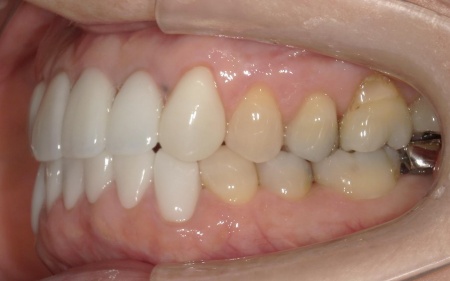

1:左上前歯2本と左右下前歯2本に装着されていた被せ物を外し、先に再根管治療を行う。

2:メタルコアを除去し、白い樹脂製のファイバーコアを用いて土台を修復する。

ファイバーコアは自費診療なので比較的費用がかかり、メタルコアよりも強度は劣るため症例によっては使用できませんが、天然歯に近いしなやかさがあり、歯根が割れるリスクを低減できる点がメリットです。

3:色味に違和感がある被せ物を除去し、左上前歯2本と下前歯6本は、天然歯に近い色が出せる「セラミック」の被せ物を装着する。

今回は被せ物の素材として、セラミックの一種である「ポーセレン前装ジルコニア」を選択しました。

ポーセレン前装ジルコニアは、内側には硬くて丈夫なジルコニアが用いられ、外側にはポーセレン(陶材)が焼き付けられており、審美性と強度のバランスに優れている被せ物です。ただ、強い力がかかると外側のポーセレンが欠けるリスクがあります。

4:右上前歯3本と左上前歯1本には、表面に薄いセラミックの板を貼り付けて色や形を整える「ポーセレンラミネートベニア」を行う。

強い衝撃で割れたり、噛み合わせによっては使用できなかったりしますが、歯をほとんど削らずに自然な見た目を再現することが可能です。